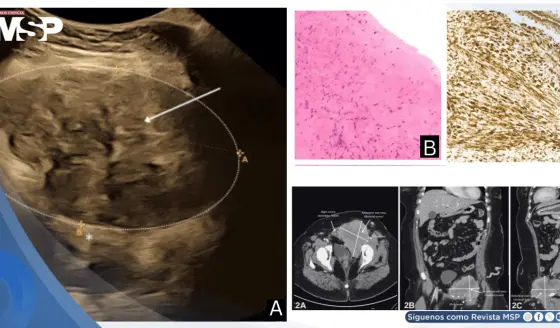

Múltiples fracturas costales por osteorradionecrosis como secuela de la reirradiación por cáncer de mama